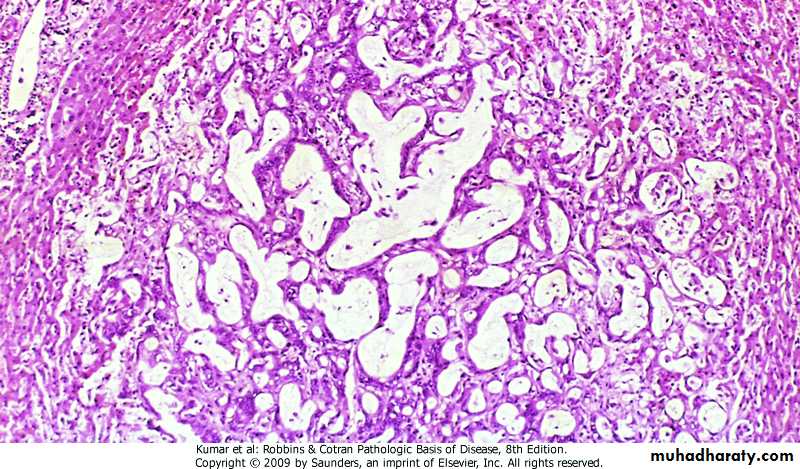

Carcinoma In Situ (CIS).dysplasia involving entire thickness of epithelium & remains confined by basement membrane

Carcinoma In Situ